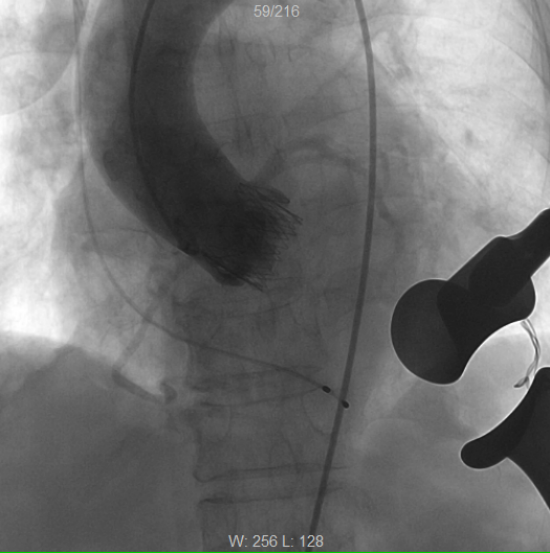

术前造影,提示主动脉瓣在舒张期出现大量返流